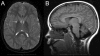

Figure 2 Pattern on brain MRI (A) High globus pallidus iron (arrow) on T2-weighted imaging in a 9-year-old patient with atypical neuroaxonal dystrophy and PLA2G6 mutations. (B) Cerebellar atrophy (arrow) is evident in a case of classic infantile neuroaxonal dystrophy.